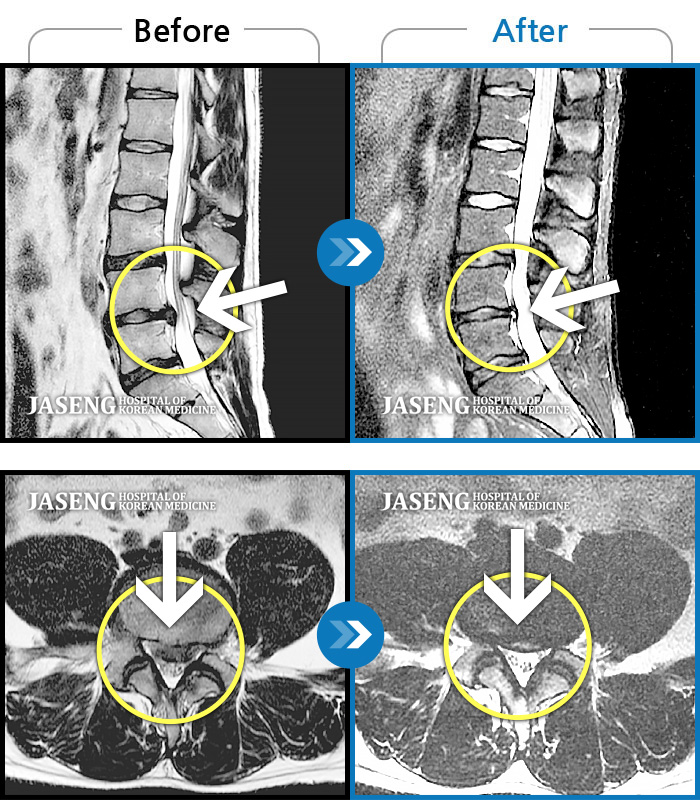

허리디스크

강남 · 강만호 원장

집에서 무거운 물건 들다 삐끗한 후 허리디스크가 터지고 흘러내려 극심한 통증을 호소하셨습니다

촬영시기

2019.05.23 ~ 2023.09.05

2023.09.22

조회수 177